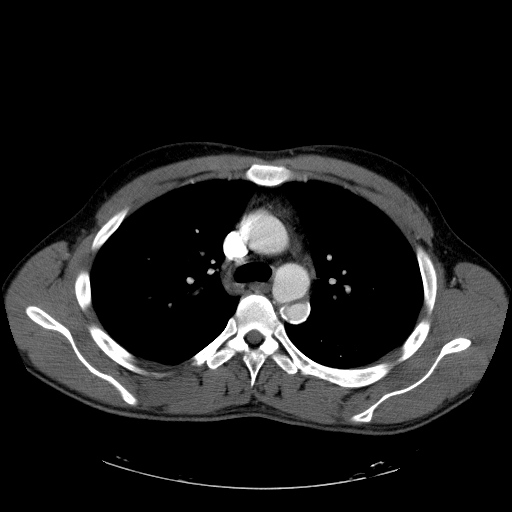

Скидываю сканы КТ-органов брюшной полости, сразу отмечаю, что специальная матодика для отценки стенок желудка не проводилась но на фоне рентген-контрастного вещества отмечается утолщение стенок антрального отдела желудка;

Уважаемый Валентин Львович, мои старшие коллеги с опытом работы тоже самое мне предложили в проведении диф.диагностики. буквально на следующий день после проведения было сделано целенаправленное взятие биопсии где наши патоморфологи подтвердили, а еще через пару дней с целью исключения метастазов при проведении КТ-органов брюшной полости видно было четко на сканах мягко-тканный компонент опухоли желудка, сканы с вашего разрешения предоставлю завтра.

Красными стрелочками отмечено наличие мягко-тканного компонента инфильтративного роста.